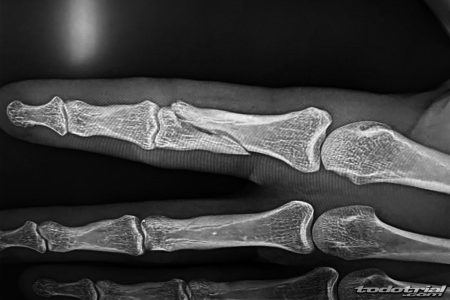

El propio piloto anunció así la lesión a través de sus redes sociales, acompañando el mensaje con una radiografía: «Malas noticias!! Una fuerte caída en el GP de USA nos va a dejar parados un tiempo!! Fractura en el índice de la mano izquierda. El jueves pasaremos por quirófano para estar de vuelta lo antes posible.»

Este tipo de fractura suele requerir la colocación de una placa con tornillos, lo que podría acelerar su recuperación en comparación con lesiones de ligamentos. Sin embargo, el piloto se verá obligado a ausentarse de la próxima prueba doble del Campeonato de España de Trial, que tendrá lugar los días 26 y 27 de julio en Pobladura de las Regueras (León).